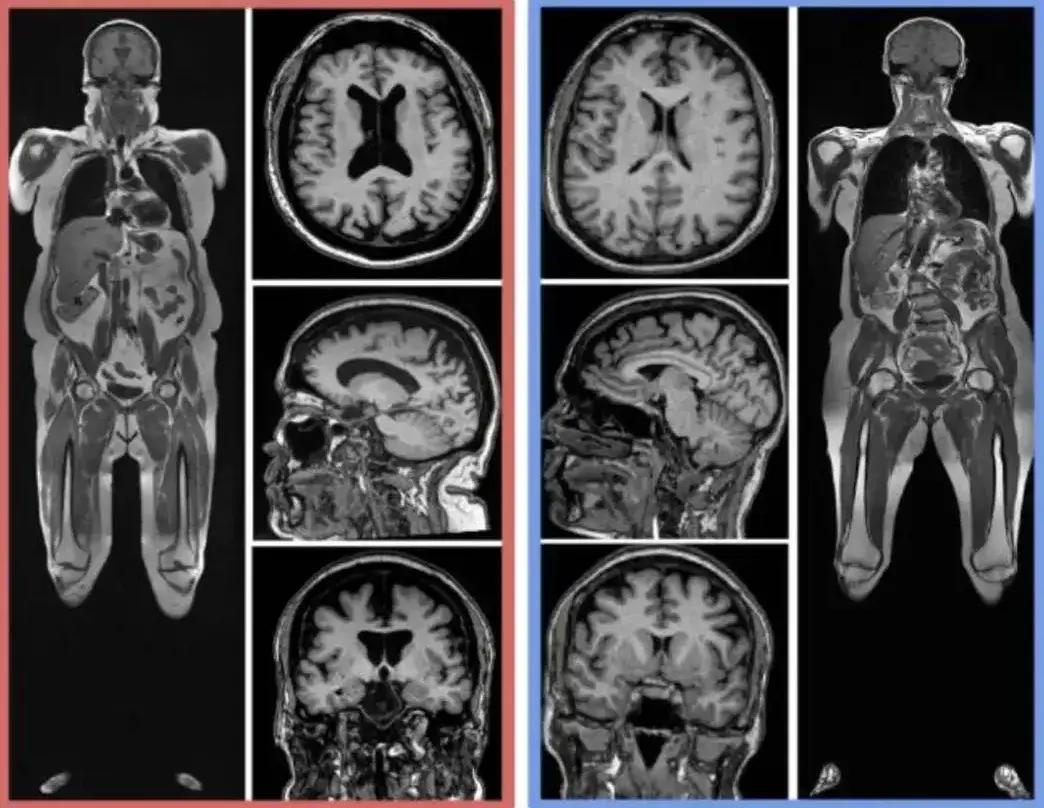

左側受試者,四肢和腹部有更多脂肪(亮色區域),大腦體積更小。

隊列研究顯示,較高的BMI與較小的大腦總體積、灰質體積相關,還與較大的白質病變體積有關。

進一步分析發現,顯著的腦灰質體積萎縮主要發生在額葉(參與認知處理、注意力、推理、閱讀流暢性和語言理解)、顳葉(記憶)和前扣帶回(負責認知、注意力)

在年齡小於45歲的參與者中,累積BMI較高與較小的腦實質、灰質體積更顯著,腦實質體積縮小17.9毫升,灰質體積縮小13.4毫升,腦脊液體積增加17.9毫升。

對於小於45歲的人,累積BMI>26.2,大腦體積的變化相當於大腦衰老了12年。

在60歲以上的人羣中,累積BMI較高與較大的白質病變體積有關,白質病變體積增加了6毫升。